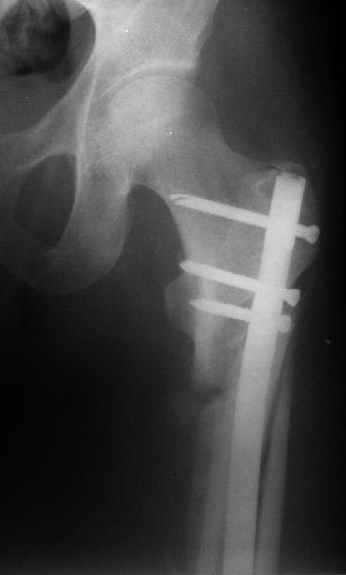

При межвертельных переломах с цефаломедуллярными гвоздями бывает, что проксимальый винт проходит или черед периферический отломок, или прямо над ним. И если остался диастаз, то этот винт при осевой нагрузке не дает сблизиться отломкам. Пример такого остеосинтеза в застарелом случае в приложении.

В качестве предупреждающей меры можно долотом разрушить латеральную стенку дистального отломка под винтом.

В частности, на проксимальном конце сделано еще одно дополнительное статическое отверстие. Можно ввести в проксимальном отделе 4 винта, из них 3 статические (2 в круглые отверстия и 1 по нижнему краю овального). Картинки в приложении. На дистальном конце стержня тоже кое-что улучшено. Спрашивайте в аптеках, как говорится. Выпускается предприятием "ЦИТО" (Москва), то есть это малобюджетное решение.

Картинка красивая, но на мой взгляд, не совсем оптимальная: Слишком медиально введён стержень - риск аваскулярного некроза головки бедра.

вариант межфрагментарного шинирования - зона достаточно простительная т.е. чрезвертельные переломы потенциально хорошо срастаются при любом

расположении сопредельных отломков- хорошая локальная васкуляризация. В приведённом случае я бы предпочёл принцип межфрагментарной компрессии (рекон/гамма нэйл 130- 135) принципу шинирования перелома.

Это было года 2,5 назад, мы тогда еще уточняли возможности шинирования с угловой стабильностью гвоздем с поперечным расположением винтов при переломах проксимального отдела бедра. Пациенту не пришлось приобретать намного более дорогой рекон или проксимальный гвоздь. В приложении еще несколько примеров применения того гвоздя при высоких переломах бедра, в том числе с более латеральной точкой входа. Гвоздь изгибаем для этого.